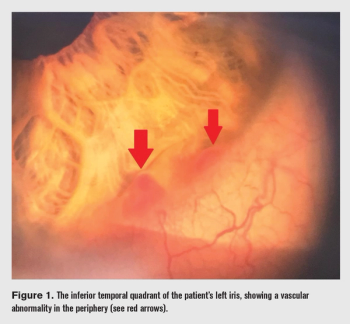

Case shows need to investigate further to provide patients with the correct treatment.